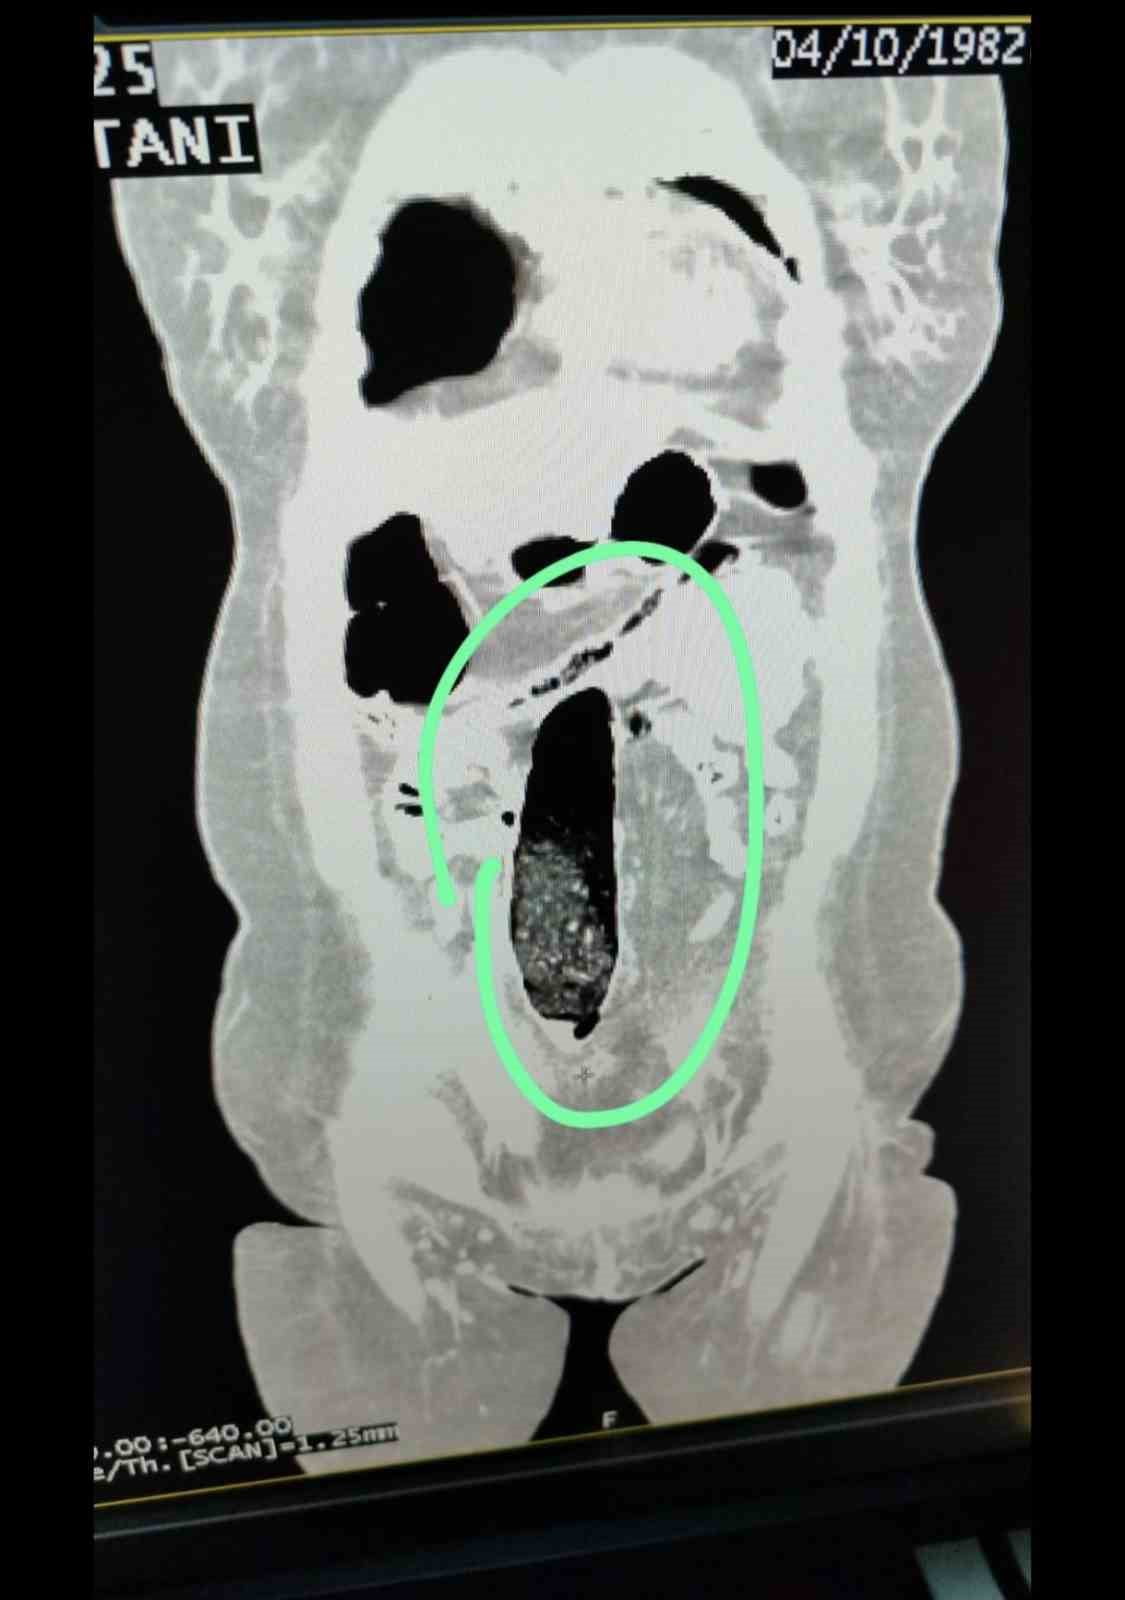

Tıbbi Müdahale ile Uyuşturucu Ele Geçirildi

Şahısların iç beden muayeneleri sonucunda, doğal boşluklarında ve bağırsaklarında uyuşturucu maddelere rastlandı. F. V. isimli kadın şahıstan 397,78 gram metamfetamin, S. İ. isimli erkek şahıstan ise 24 adet sentetik hap ve 167,68 gram metamfetamin ele geçirildi.